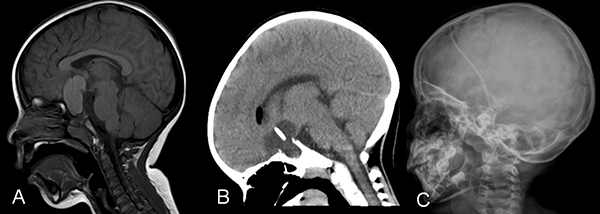

En los últimos años, se fue instalando una tendencia a un mayor interés a preservar la calidad de vida de los niños y adolescentes con craneofaringiomas.31 El mejor tratamiento para los craneofaringiomas pediátricos ya no sólo involucra la resección completa de la lesión sino la preservación de la función endocrinológica.32 Estos tumores son de crecimiento lento y requieren de un tratamiento crónico, siendo importante recordar que en la población pediátrica la mayoría de los tumores son quísticos y de gran tamaño (más del 60% del volumen tumoral).5,11,32 A partir de esta premisa es que han surgido procedimientos menos invasivos como el uso del sistema de Ommaya, que provee alivio de los síntomas y permite retrasar la cirugía agresiva hasta la completa maduración del eje hipotálamo-hipofisario(figura 2).29

Figura 2. Tomografía cerebral simple. A y B. Cortes coronal y sagital donde se observa un tumor predominantemente quístico con cápsula parcialmente calcificada. C y D. Cortes coronal y sagital postoperatorio con catéter colocado dentro del quiste tumoral para reducción progresiva del volumen del mismo. Se observa reservorio a nivel subgaleal.

El tratamiento de craneofaringiomas mediante Ommaya ha pasado por diferentes estadios. Las primeras series trataban el quiste con Bleomicina,11,34 luego se intentó el tratamiento con Inteferón donde el equipo del SickChildren de Toronto presentó resultados muy alentadores,34 y por último la aspiración del quiste sin introducir ninguna sustancia.5 Drenar el quiste mediante el sistema de Ommaya es útil ya que permite que se reduzca el tamaño de la lesión y disminuye el contacto con las estructuras circundantes. Se encuentra descripto que luego de múltiples drenajes del quiste, la exéresis de la lesión es menos dificultosa debido a que presenta menos adherencias al hipotálamo, a la carótida interna o al quiasma.33 Otra ventaja del drenaje del quiste es que permite desbloquear los forámenes de Monro y mejorar la hidrocefalia obstructiva.3 Si bien nuestra serie de pacientes con Ommaya es muy reducida para sacar conclusiones definitivas, no encontramos un empeoramiento de las evaluaciones clínicas de los pacientes en el postoperatorio. Sin embargo, sólo 2 pacientes se mantuvieron estables luego del tratamiento, en los otros 5 casos se requirió de un tratamiento alternativo. Esto no debería considerarse como un mal resultado ya que la finalidad de la colocación del Ommaya no es curar la enfermedad sino retrasar los síntomas para permitirles a los pacientes una correcta maduración del eje (figura 3).

Figura 3. A. Resonancia cerebro corte sagital donde se observa tumor a predominio quístico en la región selar supraselar compatible con craneofaringioma. B. Tomografía de cerebro corte sagital postoperatoria de colocación de catéter intraquístico. C. Radiografía cráneo perfil donde se observa catéter radiopaco con extremo en la región selar.